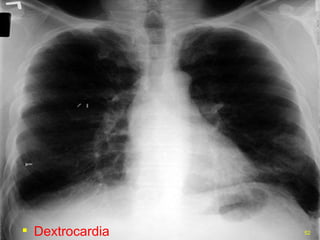

Dextrocardia